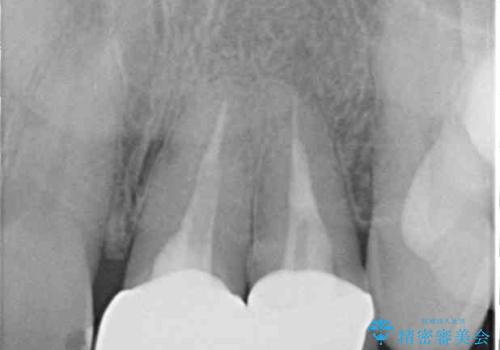

- 以前に他院で装着した前歯のオールセラミッククラウンが気になるとのことで来院された患者様です。

真ん中のオールセラミッククラウンを正面から見ると大変自然に仕上がっているのですが、側方から見ると白色が強く、さらには隣の歯は神経が除去されて変色していたため、コントラストでより色の違いが際立っていました。

前歯2本をオールセラミッククラウンにて補綴治療することとしました。

仮歯を装着した時点で、口元が気にならなくなったので、患者様が感じていた違和感の原因は変色した前から2番目の歯であったと思われます。

形態や色彩が左右対称となるように仕上がり、患者様には大変満足していただきました。